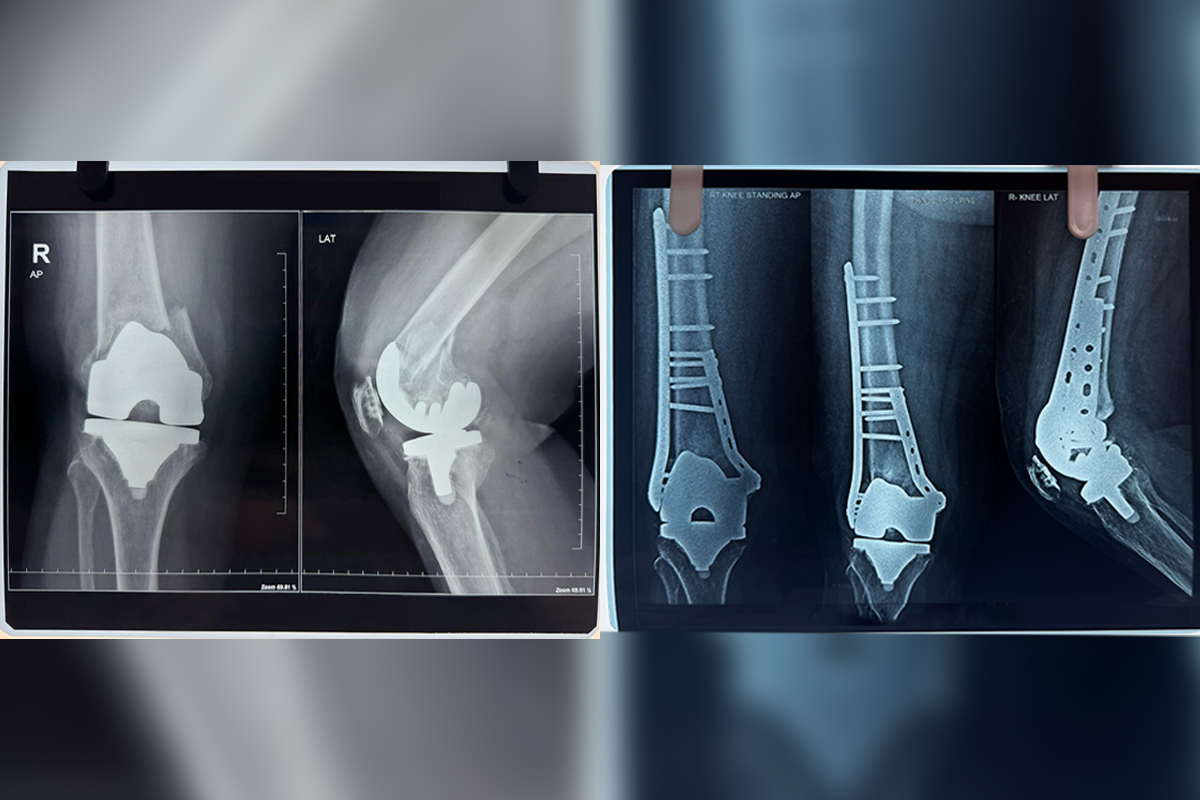

Primary Knee Replacement

Revision Knee Replacement is a surgical procedure to replace a previously implanted artificial knee joint that has worn out or failed...

Revision Knee Replacement

Periprosthetic Fractures

Periprosthetic Fracture refers to a broken bone near an artificial joint, often requiring surgical intervention for repair and stabilisation...